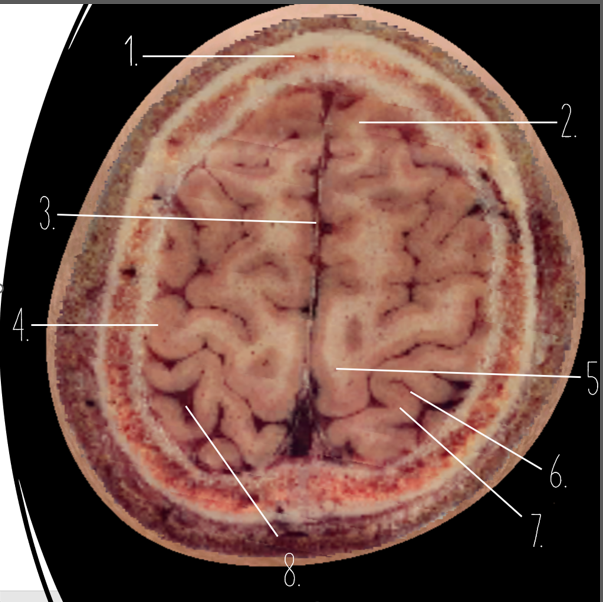

Brain Cross Sectional

1

Frontal Bone

2

Frontal Lobe

3?

Falx Cerebri

4?

Gray Matter

5?

White Matter

6?

Sulcus

7?

Gyrus

8?

Fissure